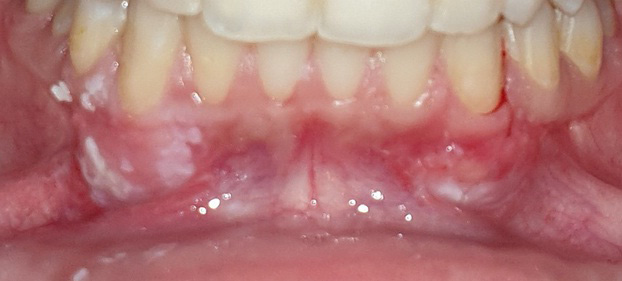

As to the healing index, there were no significant differences between the 2 sites after 1 week, 2 weeks, 1 month, and 2 months. However, the healing process was completed 1 month postoperatively in the tissue adhesive group, whereas in the suture group, it lasted up to 2 months (Table 5) (Figure 5, Figure 6, Figure 7).

One of the important issues in FGG surgery is the graft and recipient site healing. We found that the tissue adhesive significantly reduced the time needed for healing the wound and accelerated wound healing. Approximately, we achieved complete wound healing at the tissue adhesive side after 1 month. On the other hand, a 2-month period was needed for complete wound closure at the suture side. Paknejad et al. found a significant difference between the 2 groups in the healing process after 10 days, though there were no significant differences in the healing process after 20 and 90 days.29 It might be due to the fact that they used an ethyl 2-cyanoacrylate-based tissue adhesive; the component is short-chained and rarely used, as it degrades very rapidly and allows for the subsequent formation of formaldehyde, which is very toxic.32